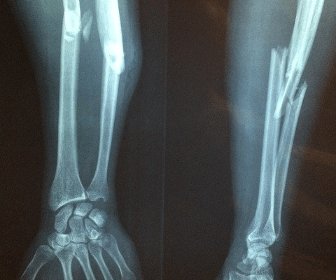

Broken Bones

Breaking bones, any bone, can be very painful and scary. Breaks can range from a minor fracture to requiring extensive surgery to fix. It's also common for the tissue surrounding the broken bones to become damaged, which can cause chronic pain and neuromuscular dysfunction.

One of the most common bones to break in a slip and fall accident is the hip bones. While a broken hip is most often associated with older people, in a slip and fall accident, anyone can break their hip. This injury can be devastating, requiring surgery and a long recovery. This is even more true for the elderly.